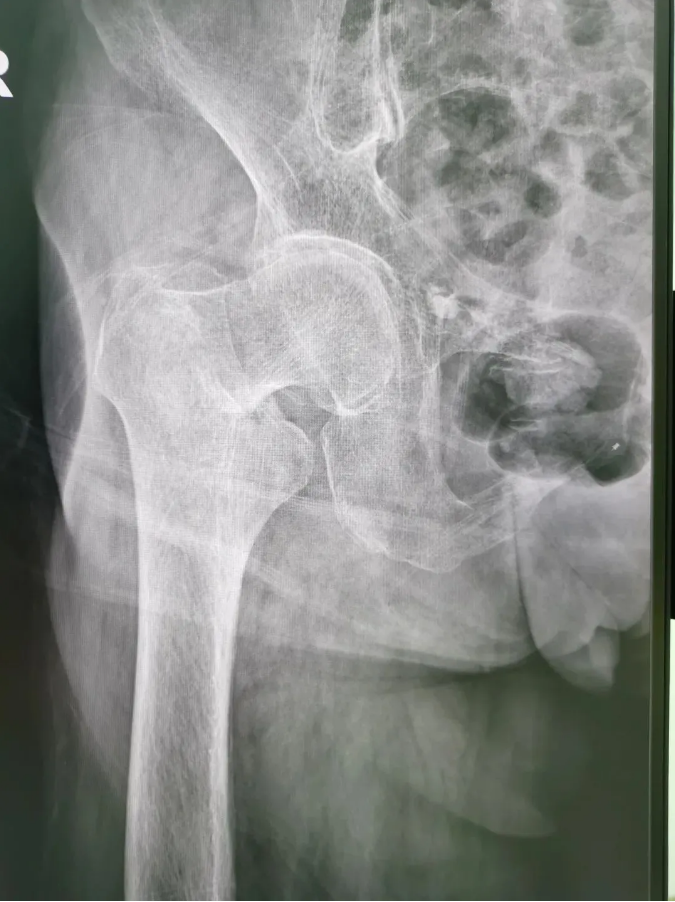

ÊõǰX¹â

½ñÄê91ËêµÄ³ÂÆÅÆÅ£¬£¬£¬£¬£¬9Ô·ÝʱÔÚ¼ÒʧÉ÷ˤµ¹£¬£¬£¬£¬£¬ÓÒÍβ¿×ŵأ¬£¬£¬£¬£¬µ±Ï¸ÐÓ¦÷Ų¿Ç¿ÁÒÌÛÍ´²¢Ô˶¯ÊÜÏÞ¡£¡£¡£¡£¡£¡£ÎªÇó½øÒ»²½ÖÎÁÆ£¬£¬£¬£¬£¬µ½Ë³µÂÇå¾²Íâ¿ÆÒ½Ôº¹ÇÈýÇø¾ÍÕ£¬£¬£¬£¬¸ÃÇøÖ÷ÈÎÑîÉýƽÖ÷ÈÎΪÆäÕïÁÆ£¬£¬£¬£¬£¬±»Õï¶ÏΪ¡°ÓҹɹǾ±¹ÇÕÛ¡±£¬£¬£¬£¬£¬Ðè¾ÙÐÐÓҹɹǾ±¹ÇÕ۾Ƥ±ÕºÏ¸´Î»¿ÕÐÄÂݶ¤ÄÚÀο¿ÊÖÊõ¡£¡£¡£¡£¡£¡£